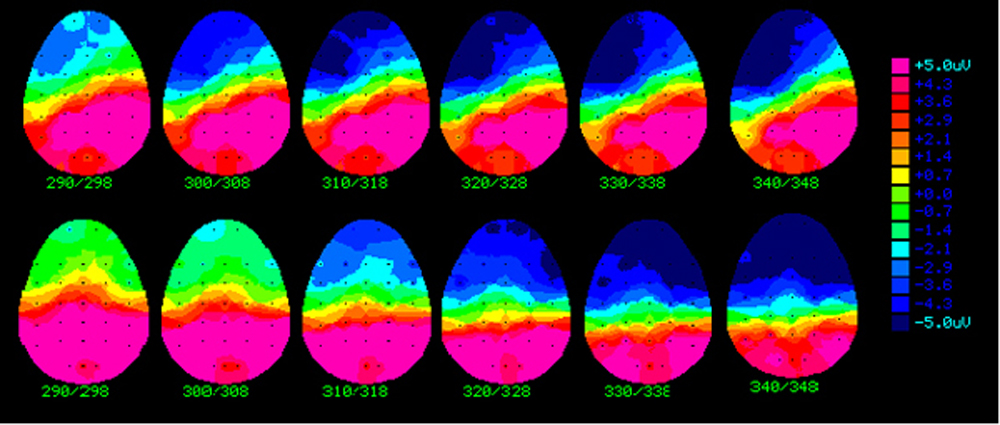

Weber-Fox, a cognitive neuroscientist, teamed with Anne Smith, a professor of speech science who studies the neurophysiological bases of speech production, to study language and speech production systems. A series of studies were conducted to measure semantic (word meaning in sentence processing), grammatical and phonological (sounds of the language, such as rhyming) aspects of language. In each study, the brain activity of adults who stutter and don't stutter were measured when they responded silently, by pressing a button, to questions regarding sentence meaning, grammar or sentence structure, and rhyming. This is believed to be the first time brain electrical activity has been studied in a series of language tasks in people who stutter to determine whether their brains function differently even when there are no overt speaking demands. The researchers' findings will be presented Friday (July 23) in Portland, Ore., at the American Speech-Language Hearing Association's conference on Fluency and Fluency Disorders. Their study, "Phonologic Processing in Adults Who Stutter: Electrophysiologic and Behavioral Evidence," is scheduled to be published in the December issue of the Journal of Speech, Language and Hearing Research. The research was funded by the National Institutes of Health. "Adults who stutter often have great language skills, meaning they don't have problems with rules of grammar or with the sounds we use to code the words of our language," Weber-Fox says. "When they speak, however, their motor output falters, so they pause or trip over words. We wanted to evaluate the brain activity when they were not stuttering and, in fact, when they were not having to engage their speech motor systems." Smith, who also is head of Purdue's Department of Audiology and Speech Sciences and has been studying the physiological aspects of stuttering since 1988, says, "Our research found many complex interactions between the language and motor systems, which leads us to believe that there is no single cause for stuttering. Stuttering is the result of a complex interaction among many factors, including genetic, language, motor and emotional. But our research found many complex interactions between the language and motor systems, which leads us to believe that there is no single cause for stuttering. These findings will help reduce the stigma such as the myth that the disorder is the result of poor parenting or a psychological problem often associated with stuttering." Stuttering, which interrupts the flow of speech, affects 5 percent of people in the United States at some time in their lives. Stuttering usually begins in the preschool years, and there is a higher incidence in males. Characteristics of the disorder can range from repetition of sounds, prolongation of syllables, elongated pauses between words and speech that occurs in spurts. Weber-Fox and Smith's most recent study focused on phonological aspects of language, specifically rhyming. Just as in the earlier studies that evaluated responses to semantic and grammar language tasks, brain activity was measured in milliseconds. This non-invasive technique uses a skull cap with electrodes to measure activity for groups of brain cells. Response accuracy and time also were measured in this study. In the rhyming study 22 subjects, half of whom stutter, saw a series of two words flash on a computer screen. Their task was to identify which pairs of words rhymed without saying the word out loud. Some word groups were spelled alike but did not rhyme, such as "gown" and "own," and others did not look similar but did rhyme, such as "cone" and "own." The other variations were words that looked similar and did not rhyme, such as "gown" and "own," and words that did not look similar or rhyme, such as "cake" and "own." This method evaluated the adults' ability to translate sounds when not verbalizing them. The researchers found that individuals who stutter experienced similar brain activity, response accuracy and response time when it came to three of the four rhyming variations. For example, if two of the words look alike and rhyme, such as "thrown" and "own," most people can quickly identify that they rhyme. But if two words look alike but didn't rhyme, such as "gown" and "own," then the response was delayed to 410 milliseconds for those who stutter. The other three variations averaged about 350 milliseconds among all participants. "We saw no difference in the fundamental processing when looking at words like gown and own," Weber-Fox says. "The difference was in the complexity of the language task. Also of note during this study was the increase in activity in the brain's right hemisphere for participants who stuttered as they viewed the rhyming words. This shows the individuals who stutter are using right hemisphere brain areas to a greater extent to accomplish the rhyming tasks than those who don't stutter." Weber-Fox says this relationship to the right hemisphere is a consistent finding that has been shown in other forms of brain imaging, such as functional magnetic resonance imaging. The right hemisphere is considered the non-dominant hemisphere for language, and the activity may indicate that the right hemisphere is compensating for something that is not happening in the left hemisphere, she says. In similar experiments, the researchers are now looking at stuttering in children and are introducing a hearing task for adults who stutter. "We looked at the brain's reaction when reading words, and now we are focusing on hearing words," Weber-Fox says. "Do we see atypical responses when somebody who stutters is listening to sentences instead of reading them? We have preliminary data that suggests yes." Purdue's Department of Audiology and Speech Sciences is ranked among the top 10 in the nation by U.S.News & World Report. The master's and doctoral degree program in speech-language pathology and audiology are ranked third and eighth, respectively. Writer: Amy Patterson-Neubert, (765) 494-9723, apatterson@purdue.edu Sources: Christine Weber-Fox, (765) 494-3819, weberfox@purdue.edu Anne Smith, (765) 494-3788, asmith@purdue.edu Purdue News Service: (765) 494-2096; purduenews@purdue.edu Note to Journalists: The researchers' findings will be presented July 23 in Portland, Ore., at the American Speech-Language Hearing Association's conference on Fluency and Fluency Disorders. PHOTO CAPTION: A publication-quality photo is available at https://ftp.purdue.edu/pub/uns/+2004/weberfox-research.jpg GRAPHIC CAPTION: A publication-quality graphic is available at https://ftp.purdue.edu/pub/uns/+2004/weberfox-research2.jpg Phonological Processing in Adults Who Stutter: Electrophysiological and Behavioral Evidence Christine Weber-Fox, Rebecca M.C. Spencer, Event-related brain potentials (ERPs), judgment accuracy and reaction times (RTs) were obtained for 11 adults who stutter and 11 normally fluent speakers as they performed a rhyme judgment task of visually presented word pairs. Half of the word pairs (i.e., prime, target) were phonologically and orthographically congruent across words. That is, the words looked orthographically similar and rhymed (e.g., THROWN, OWN) or did not look similar and did not rhyme (e.g., CAKE, OWN). The phonologic and orthographic information across the remaining pairs was incongruent. That is, the words looked similar but did not rhyme (e.g., GOWN, OWN) or did not look similar but rhymed (e.g., CONE, OWN). Adults who stutter and those who are normally fluent exhibited similar phonologic processing as indexed by ERPs, response accuracy and RTs. However, longer RTs for adults who stutter indicated their greater sensitivity to the increased cognitive loads imposed by phonologic/orthographic incongruency. Also, unlike the normally fluent speakers, the adults who stutter exhibited a right hemisphere asymmetry in the rhyme judgment task, as indexed by the peak amplitude of the rhyming effect (difference wave) component. Overall, these findings do not support theories of the etiology of stuttering that posit a core phonologic processing deficit. Rather we provide evidence that adults who stutter are more vulnerable to increased cognitive loads and display greater right hemisphere involvement in late cognitive processes.